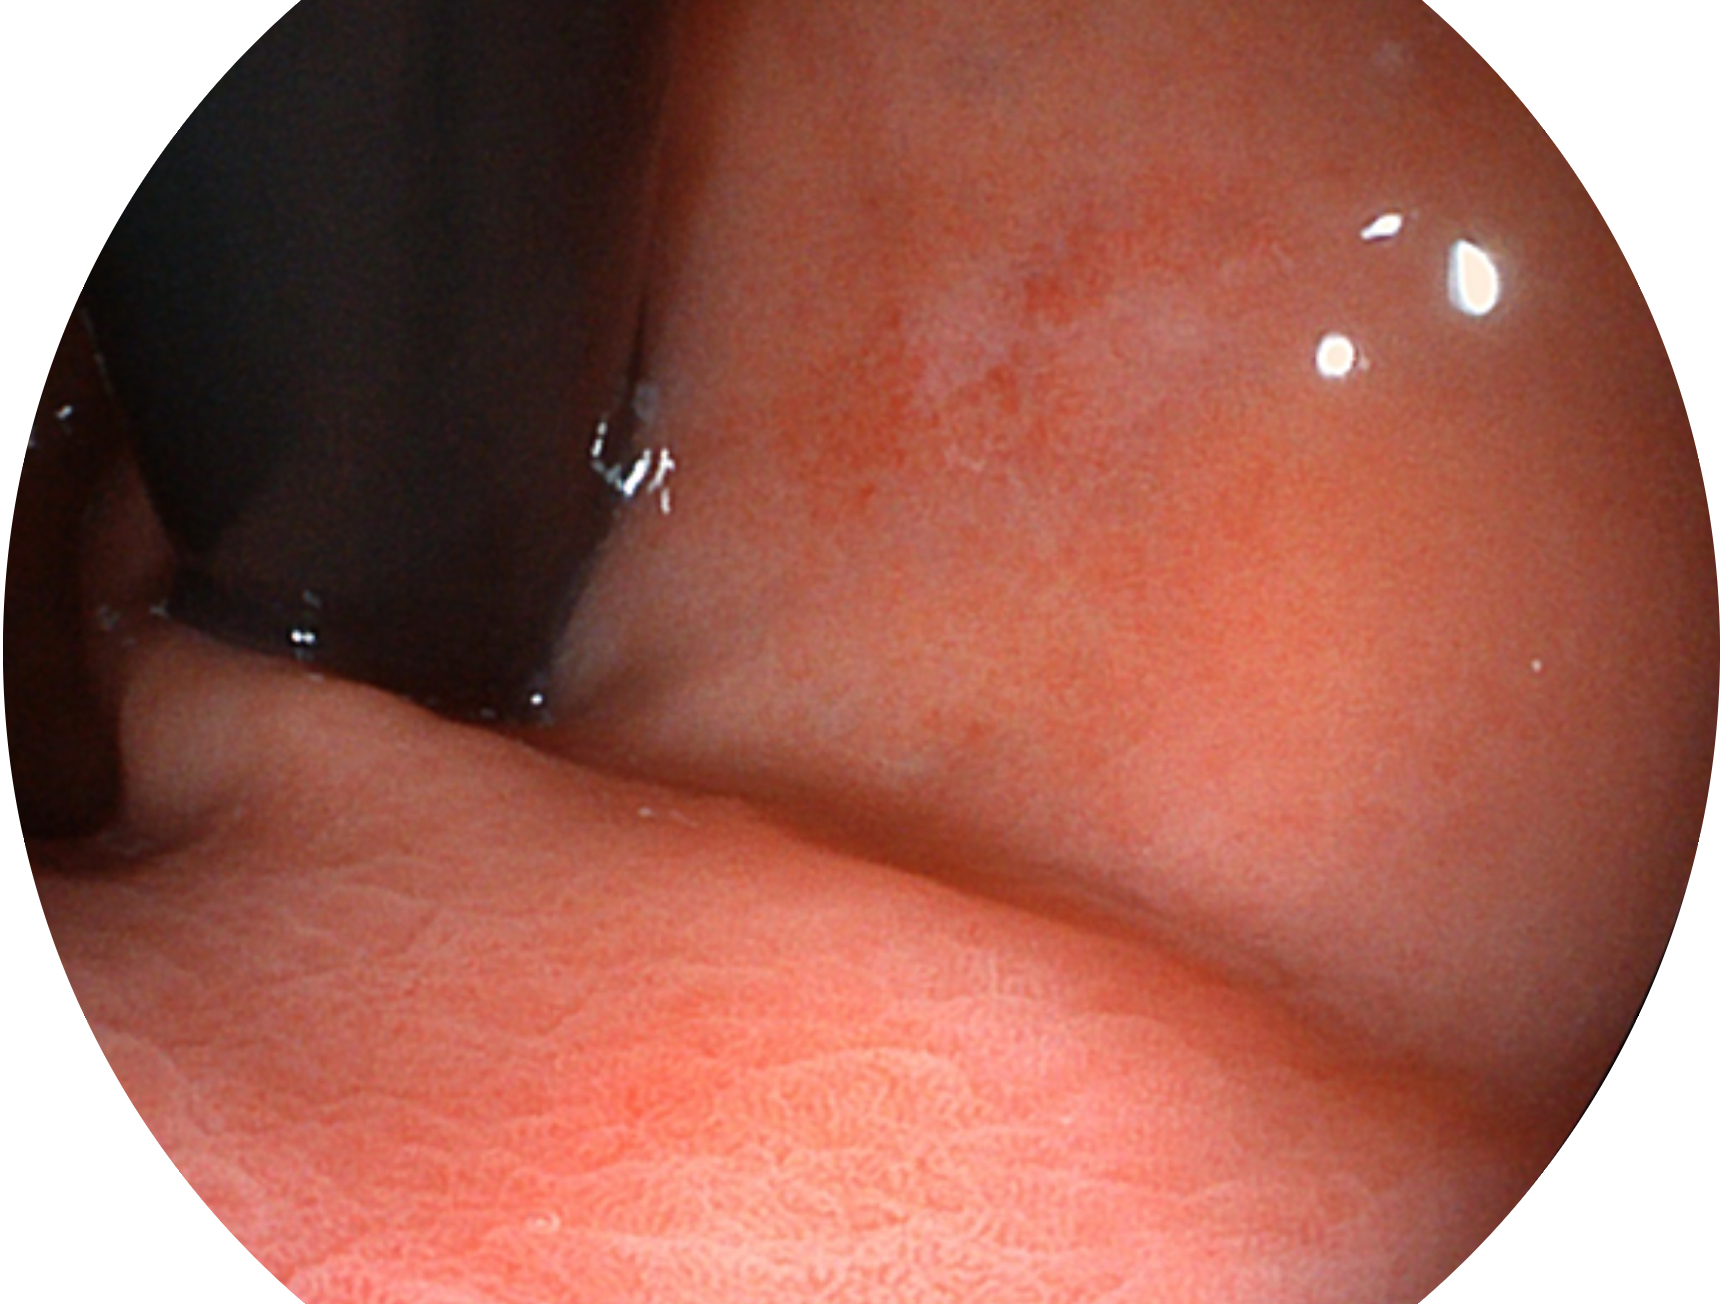

開立新開發(fā)的內(nèi)鏡染色技術(shù),主要是基于多波長(zhǎng)LED 光源的開發(fā),VLS-55Q 四波長(zhǎng)LED 光源是由四個(gè)不同顏色的LED光按照相應(yīng)照明模式所規(guī)定的特定發(fā)光比例進(jìn)行合束后形成,合束后形成的照明光的光譜由紅光、綠光、藍(lán)光及藍(lán)紫光這四個(gè)不同的波段范圍構(gòu)成。具有更高光譜自由度,通過光譜比例的控制,實(shí)現(xiàn)了聚譜成像技術(shù),英文全稱為“Spectral Focused Imaging, SFI”,縮寫為“SFI”和光電復(fù)合染色成像技術(shù),英文全稱為“Versatile Intelligent Staining Technology, VIST”,縮寫為“VIST”。